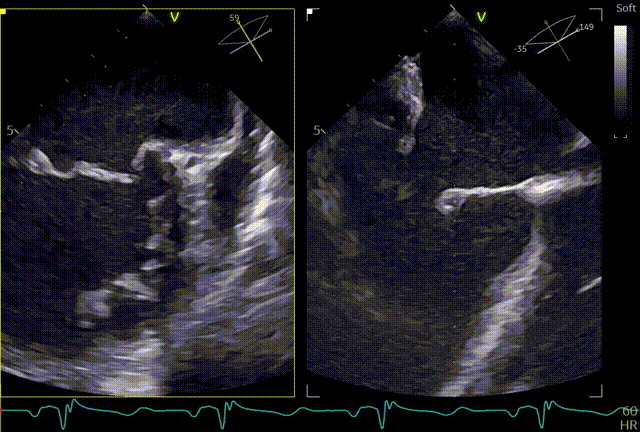

术前TEE及左房压

1区

1区带彩

2区

2区带彩

3区

3区带彩

3D

3D带彩